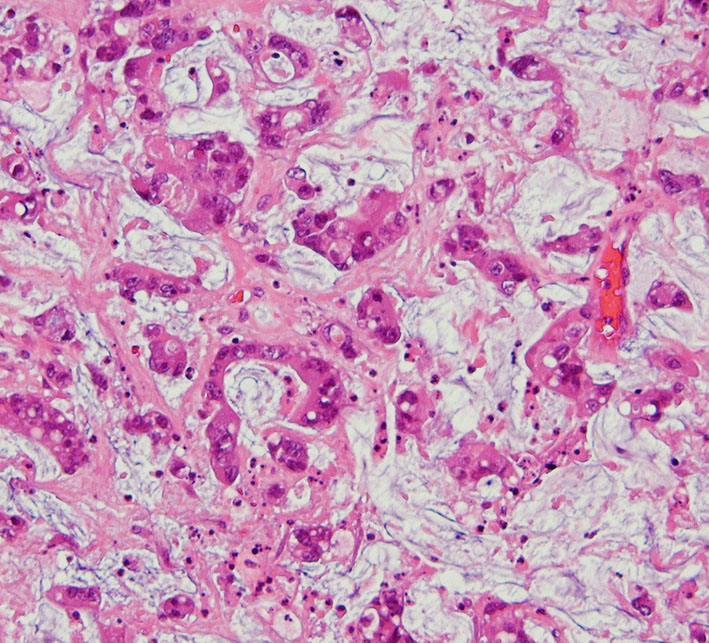

左側頭葉への腎癌の単発転移です。症候性てんかん(失語症発作)で発見され,定位放射線治療を受けたのですが,数ヶ月後に脳浮腫が高度となり失語症が悪化しました。コアになっている円形の転移腫瘍の周囲に放射線による脳壊死を疑いました。2時間ほどの開頭手術で,右側のガドリニウム増強されているところだけを摘出しました。

腫瘍中心の壊死の部分です。腫瘍細胞が死滅して凝固壊死の像です。血管はヒアリン化して閉塞しています。

腫瘍の辺縁部で手術中に血管が発達して出血があった部分です。腫瘍細胞 clear cell carcinoma が新生血管周囲に増殖しています。真ん中はPAS染色,右側はMIB-1染色で13%くらいの高い陽性率です。これは定位放射線治療で腫瘍が全部死滅していなくて一部では再発していることを示します。

さらに周辺と正常脳との境界部位です。脳組織が壊死になっていてます。放射線脳壊死が周囲にあって,高度の脳浮腫を生じていたことがわかりました。

この例は,定位放射線治療後に,1) ガン組織が壊死になって放射線治療の効果が認められる,2) ガン転移の再発がある,3) 放射線脳壊死が起こっている,という3つの事象が混じって生じているものです。ですから,PETやMRSなどで手術の前の画像診断を頑張ってみても,診断がつくはずがないのです。病理診断しか手段がありません。

手術1年半後の画像です。症状はなくて元気にお暮らしでした。新たな脳転移はありません。

この患者さんは幸運な方といえます。ガンを見る内科の先生に知っていただきたいのですが,今でも脳神経外科の手術は転移性脳腫瘍の治療に役に立つことがあります。